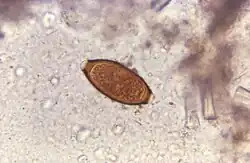

При микроскопии кала обнаруживают яйца возбудителя размерами 50х20 мкм, по форме напоминающие лимон. Половозрелые власоглавы имеют длину 3-5 см и иногда видны при ректороманоскопии.